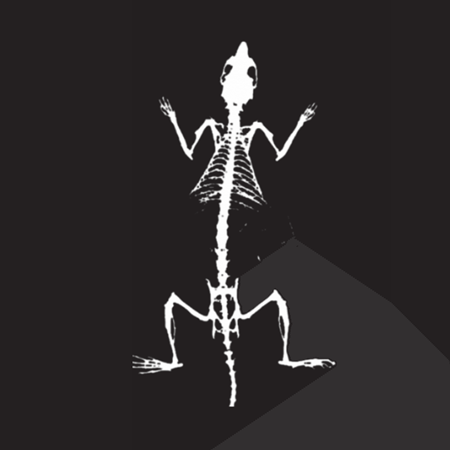

The iNSiGHT technology employs dual energy X-rays to provide highly accurate and repeatable body composition assessments. The system categorizes each pixel into one of three compartments: fat mass, non-bone/lean mass, or bone mineral content, and provides measurements such as bone mineral density, bone mineral content, bone area, tissue area, fat tissue percentage and weight, lean tissue percentage and weight, and total weight in grams.

With this noninvasive, nondestructive method, no contrast, substrate injection, or animal pretreatment is necessary. The 2D X-ray image can also be used with the iNSiGHT system to determine precise bone length measurements.

The X-ray attenuated image, bone mineral density map, and color map are produced in a single scan (25 seconds).

X-Ray Attenuation Image - Rat. Image Credit: Scintica Instrumentation Inc